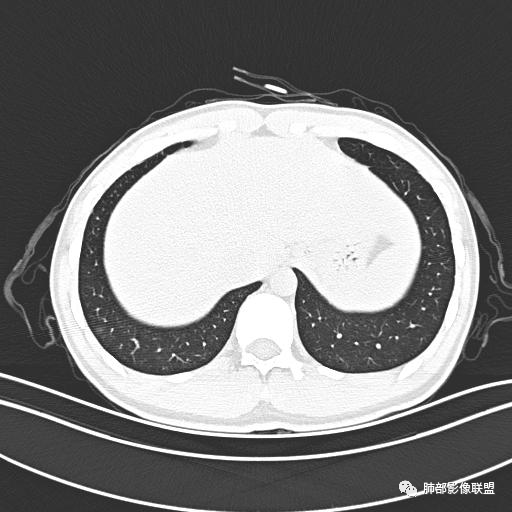

男,19岁

主  诉:发热、全身皮疹2天。

现病史:患者源于2天前受凉后出现发热,最高体温为38.5℃,且颜面部出现少量皮疹,无鼻塞、流涕、咳嗽、咳痰,未在意而未作特殊处理,次日全身皮疹逐渐增多至全身,伴轻度瘙痒,在当地卫生所给予抗病毒、抗感染治疗(具体用药不详)体温有所下降,但皮疹无明显消退,无腹痛、头痛,食欲无明显减退,为进一步诊治,遂于今日急来我院求治,患者目前精神尚可,体力正常,食欲正常,睡眠正常,体重无明显变化,大便正常,排尿正常。

小强:青年,发热,皮疹;双肺散在结节,周围磨玻璃,点晕征,疱疹病毒感染,鉴别荚膜组织胞浆菌,结核。 大雄:青年,急性起病,发热伴全身皮疹2天,抗病毒治疗体温有下降。双肺随机分布大小不等类圆结节,“点晕征”。考虑水痘-疱疹病毒(VZV)血播询问接触史,查体皮疹分布以及形态基本可诊断。 王开金江津中心医院呼吸科:青年男性,起病急,病程短,以发热,皮疹为首发症状,感染指标以单核细胞升高为主,胸部ct双肺多发结界,周围有晕,点晕表现,随机分布,同意於老师意见,水痘疱疹病毒血流感染累及肺。 王秀仙:双肺多发大小不等结节,周围有晕,边缘模糊,呈点晕征表现。青年,急性起病,发热伴全身皮疹2天,抗病毒治疗体温有下降。考虑疱疹病毒。鉴别荚膜组织胞浆菌。 傅昌瑜:19岁男性,发热、全身皮疹2天,单核细胞增高,双肺多发结节,结节边缘见边界不清磨玻璃影。点晕征+发热、全身皮疹+单核细胞增高——考虑水痘-带状疱疹病毒肺炎。 一切∮随缘:年轻男性,发热,皮疹两天,实验室,CRP,PCT增高,影像:双肺多发散在磨玻璃结节,边界欠清,大小不等,呈点晕征改变,以血管束周围分布为主,局部血管束略增粗,其它无明显改变,考虑:1:病毒性肺炎(水痘疱疹病毒?不知道皮肤有无改变)2:真菌(组织胞浆菌,血管侵袭性肺曲霉)3:GPA4:寄生虫(实验室没有看到嗜酸细胞增高) 赵山河:双肺散在结节,周围有晕,边缘模糊,呈点晕征表现。青年,急性起病,发热伴全身皮疹2天,抗病毒治疗体温有下降。考虑水痘—疱疹病毒感染。洪桥爱:青年男性,发热、皮疹2天,伴瘙痒,皮疹于面部首发,之后进展至全身,虽然没有对皮疹进行描述,但是从出疹时间及皮疹进展情况,伴瘙痒,应该就是个水痘患者;CT提示双肺随机分布结节影,部分结节伴有边界不清晕征,考虑水痘血播肺。 刘强:年轻男性,急性起病,皮疹,发热,抗感染治疗体温下降,说明有效。影像表现为散在点晕征,感染类疾病谱(疱疹病毒,真菌,结核),结合年龄,皮肤皮疹,考虑水痘-疱疹病毒性肺炎。 小兜:男性,19岁,发热皮疹两天,颜面部至全身,CRP,降钙素及单核增高。CT示双肺散在小结节,周围伴磨玻璃影,点晕征,考虑为水痘-带状疱疹病毒(varicella-zoster virus,VZV)肺炎 必有路:青年,皮疹+发热+“点晕征”→水痘-疱疹病毒(VZV) 许慧良:青年男性患者,发热、皮疹2天,体温最高38.5℃,第3天皮疹扩展至全身,伴瘙痒,胸部CT:双肺多发随机分布的小结节,结节周边见边界模糊的晕征,考虑水痘病毒感染流心明智:男,19,急性起病,发热伴全身皮疹2天。出疹顺序头→全身,抗病毒有效。胸部CT:两肺多发大小不等类圆形实性小结节影,随机分布,结节周围环绕GGO,边界模糊,呈点晕征。出疹特点是关键,未提示。考虑:血播病毒性肺炎,水痘-疱疹病毒?麻疹?鉴别荚膜组织胞浆菌、TB、血管炎、寄生虫等。 浪迹天涯:病灶多为5-10mm大小结节,结节周围可见磨玻璃样的晕环,常多发,可分布于肺内任何区域,考虑水痘—带状疱疹病肺炎如果短时间内有新的一个区域浸润,更加能说明,